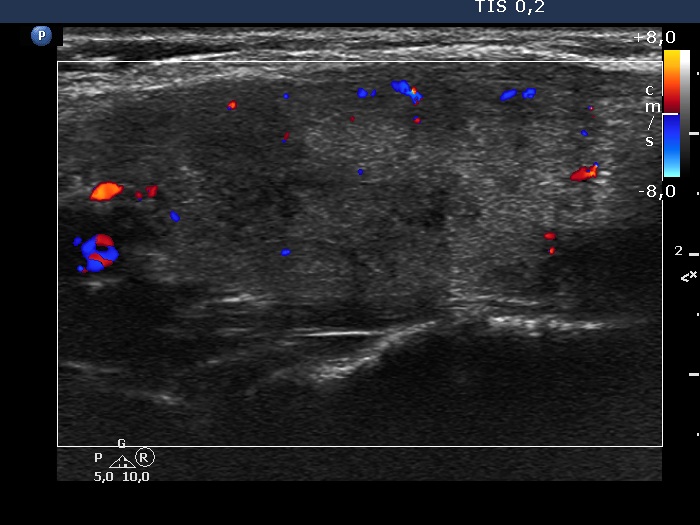

Subacute granulomatous thyroiditis - case 264

Two years after the first visit (ultrasonographic picture 6)

Left lobe, longitudinal scan. According to the hypoechoic areas, the vascularity is scanty.